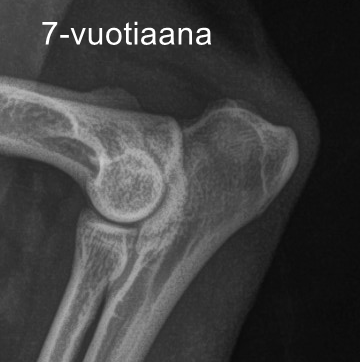

Kyynärnivelet 1/0 (Ykkösen syynä oli hiukan epätasainen nivelrako ja luultavasti sen seurauksena yläpuolen ”lovessa” näkyvä suttu.)

1. kontrollikuvaus 5-vuotiaana ja 2. kontrollikuvaus 7-vuotiaana

Kuvautin Entsyymin nivelet uudestaan hammaskivenpoiston yhteydessä. Kuvien välissä on kulunut neljä vuotta. Uudet kuvat näyttivät aika lailla samoilta kuin aikaisemmat, joten muutokset eivät ole edenneet nivelrikoksi. Päivitys: uusi kontrollikuvaus 7 v 10 kk iässä, samalta näyttää edelleen.